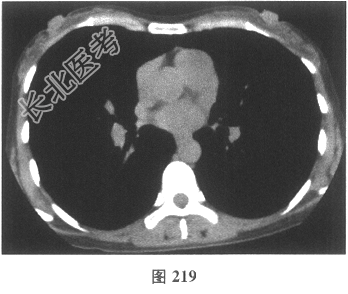

- [材料题] 患者女性,职员,43岁,以"反复咳嗽2个月余,咳痰、活动后气喘2周"就诊。体检:双肺未闻及干湿性啰音。既往无吸烟史。肺部CT见图216~图219。

- 多项选择题2.[提示]患者发病前3个月曾装修过房屋。目前考虑患者最可能的诊断为( )